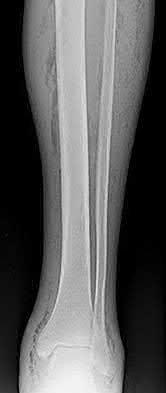

Question 19

A 28-year-old male sustains a closed comminuted tibial shaft fracture.

Two hours post-injury, he develops severe leg pain unyielding to narcotics. His blood pressure is 120/80 mmHg. Intracompartmental pressure monitoring is performed. Based on current guidelines, which measurement dictates an emergent 4-compartment fasciotomy?

Explanation

Acute compartment syndrome is classically defined by tissue hypoperfusion. The absolute compartment pressure is less reliable than the differential pressure (Delta P). A Delta P (Diastolic Blood Pressure minus Compartment Pressure) of less than 30 mmHg is an absolute indication for emergency fasciotomy, as capillary perfusion gradient is lost when tissue pressure approaches the diastolic pressure.